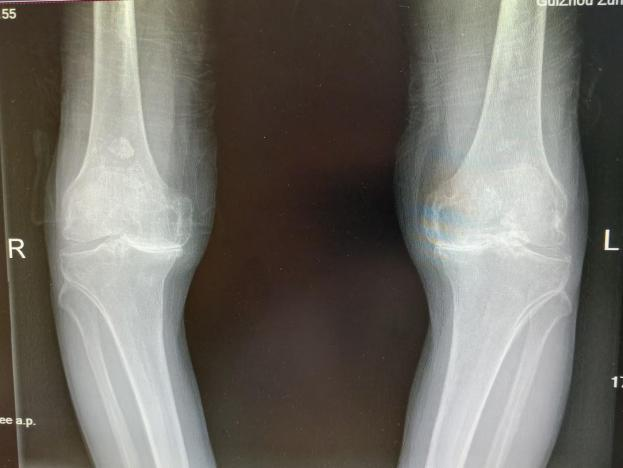

多年来,贵州航天医院各科室紧跟医学前沿,不断强技术、补短板,大力开展新技术、新项目,完成了许多高精尖、高难度、本地区“首例”的技术,填补了医院医疗技术空白,满足了群众日益增长的医疗需求。 贵州航天医院骨科率先在遵义地区开展骨搬移技术,截至目前,已治愈慢性骨髓炎、感染性骨不连、骨缺损、脉管炎、糖尿病足患者200余例,糖尿病足治疗保肢率达到98%。 本期,我们将为大家带来骨科特色技术——骨搬移技术(Ilizarov)。 案例分享 一名59岁的患者,身患糖尿病12年,在来我院3个月前出现了右脚溃烂的症状,来院就诊时,患者的右脚十分红肿,右脚脚趾坏死,伤口处不断流出黑红色脓液,情况十分严重。在接诊到患者时,骨科专家团队高度重视,立刻为患者完善了CT血管造影(CTA)等相关检查,诊断为:2型糖尿病,糖尿病周围血管病变,右糖尿病足。 术 前 考虑到患者情况比较严重,为最大限度保证患者肢体完整,科室专家团队进行了严格的讨论评估,为患者制定了骨搬移技术治疗方案,在征得患者及其家属的同意后,成功通过搬移骨块为患者进行治疗,促进患者病变肢体血管再生。 胫骨横向骨搬移外架固定 清除感染病灶 术后调节外架,通过搬移骨块 促进患肢血管再生 患者在术后三周前来换药,观察到感染得到进一步控制;术后六周复查,患者病变处已愈合,进行CT血管造影(CTA)后可明显观察到足部血管再生。 术后3周 术后6周愈合 CT血管造影见足部血管再生 糖尿病患者全身与局部的问题互为影响,形成恶性循环,糖尿病足溃疡创面迁延不愈,常见干性坏疽、湿性坏疽、趾坏死、深且大的溃疡以及骨髓炎等症状,还可导致脓毒血症,以往为保全生命,患者被迫选择一次或多次截肢。骨搬移技术的发展进步,能在血糖有效控制、局部有效清创下,有效促进患肢微血管再生,改善患肢血供,达到糖尿病足更快治疗康复的目的,并能根据病变情况最大限度的保障患者肢体完整。 什么是骨搬移技术 骨搬移技术是通过使用专用的骨外固定器固定骨段,每天缓慢牵拉,在牵拉搬移过程中,骨段尾部形成新骨及新的软组织,从而修复骨骼缺损及软组织缺损。是治疗大段骨缺损、骨不连、骨感染、肢体畸形的金标准方法,也用于治疗脉管炎、糖尿病足等肢体缺血性疾病。 骨感染缺损 切除感染段 搬移骨段 新骨形成 骨感染根治愈合 骨搬移技术原理 生物组织在持续、稳定、缓慢牵拉下,能刺激细胞分裂、组织再生,骨外固定技术运用该原理,通过持续缓慢调节外固定器形成牵拉张力,促进牵引成骨与相邻组织再生,如神经、血管、肌肉、皮肤等再生,达到治疗大段骨缺损、肢体缺血如糖尿病足等疾病的目的。 骨搬移技术优势 (一)除治疗骨缺损、骨不连外,有更广的适用范围,利用组织再生、血管再生等特性,能大量运用于肢体畸形的矫形、糖尿病足等的治疗。 (二)治疗效果确切,重建肢体外型和功能,极大降低截肢率和残疾率。 (三)明显提高了患者生活质量,极大减轻其家庭及社会负担。 肢体畸形的矫形 慢性骨髓炎 骨段切除 术后1年 濒临截肢的脉管炎术后6周 难愈创面术后3周 贵州航天医院骨科 专家团队 赵学平 骨科主任 主任医师 临床擅长:从事骨科临床工作30余年,对骨科常见疾病的诊治具有丰富的临床经验。 世界中医药联合会脊柱康复专业委员会常务理事,中华中医药学会整脊分会常务委员,中国中西医结合学会骨伤科分会肢体矫形功能重建与康复专家委员会常务委员,中国研究性医院学会骨科创新与转换专业委员会关节外科学组保髋工作委员会常委,中国康复技术转化及发展促进会骨外科与康复技术转化专业委员会常务委员,泛珠三角区域运动医学联盟(PPRD-SMA)理事会常务理事,中国研究型医院学会运动医学专业委员会委员,贵州省中医药学会整脊分会副主任委员,贵州省中西医结合学会银质针专业委员会副主任委员,贵州省康复医学会骨与关节专业委员会常务委员,贵州省人民医院骨科专科联盟常务理事,贵州省康复医学会骨内科专业委员会常务委员,中华医学会贵州省骨科学会委员,贵州省康复医学会脊柱脊髓专业委员会常务委员,贵州省运动医学分会委员,贵州省康复医学会骨与软组织肿瘤专业委员会委员,遵义市医学会创伤分会副主任委员,贵州省康复医学会骨内科专业委员会遵义地区分会常务委员,遵义市医疗事故鉴定、伤残鉴定、工伤鉴定、司法鉴定专家。 长期从事骨科临床研究及教学工作,在国家级、省部级杂志发表论文20余篇,SCI论文2篇,参与主编骨科专著2部,主持省部级科研项目2项,参与指导省部级、市级科研项目6项。 陈明勇 骨科副主任 副主任医师 临床擅长:从事创伤骨科工作约20年,对骨缺损、骨不连、骨肿瘤、肢体畸形等的肢体矫形重建及功能重建,慢性化脓性骨髓炎的根治治疗、糖尿病足的保肢治疗、快速康复理念(ERAS)下的老年骨折的诊治,四肢复杂骨折的诊治,四肢骨折等微创手术治疗具有丰富的临床经验。 2004年毕业于遵义医学院临床专业,曾在中国人民解放军总医院、广西医科大学第一附属医院、上海第六人民医院骨科进修。中国中西医结合学会骨伤科专业委员会横向骨搬移治疗糖尿病足及微血管网再生学组首届委员,遵义市医学会创伤分会常务委员。 瞿 辉 骨科 副主任医师 临床擅长:对骨科的常见病、关节外科、脊柱外科及运动医学疾病的诊治具有丰富的临床经验,熟练掌握骨科手术操作技术。 毕业于遵义医学院临床医学系,2005年前往广州中山大学第一附院骨显微医学部进修学习,2011年前往成都华西医院进修学习,并多次在省内外学习骨科相关知识,是中华医学会骨科分会会员。 赵兴东 骨科 主任医师 临床擅长:擅长骨科的常见病及各种创伤、四肢骨折创伤修复、骨感染、手足疾病的诊治和手足体表畸形的矫形整复,熟练掌握骨科四肢骨病及创伤的手术操作技术,尤其在四肢关节复杂性损伤、手足外伤、组织缺损创面、难治创面的皮瓣修复方面及平足、高弓足矫形方面及四肢慢性疼痛诊治、康复方面具有丰富的临床经验。 硕士研究生,毕业于遵义医学院临床外科系,2015年前往山东省立医院手足外科进修学习;遵义市医学分会创伤分会第一、二届委员,遵义市手外科医学会第二委届员会常务委员;在省级及省级以上期刊发表文章9篇,参编著作2部,参与主持并完成市级课题1项,参与市级课题2项、省级课题1项。 张俊凯 骨科 副主任医师 临床擅长:从事骨科临床工作28年,对创伤骨折、骨感染、骨缺损、骨不连等外科诊治,四肢骨折的微创手术治疗,四肢复杂骨折(如关节内粉碎性骨折、多发骨折等)的损伤控制及手术治疗等具有丰富的临床经验。 1995年毕业于遵义医学院临床专业,2009年前往复旦大学附属医院骨科进修1年。 卢懿明 骨科 副主任医师 临床擅长:从事骨科工作18年,对创伤骨折、四肢骨折的微创手术治疗、四肢复杂骨折(如关节内粉碎性骨折、多发骨折等)的损伤控制及手术治疗,尤其是髋部骨折的PFNA等微创技术,踝关节骨折、膝关节周围骨折的Mipo微创技术等具有丰富的临床经验,开展了4项新技术,发明6项新型专利技术。 2005年毕业于遵义医学院临床专业,2017年,前往南方医科大学第三附属医院骨科进修半年,回院后运用Mipo技术对骨干骨折及干骺端骨折的治疗技术,同时积极开展骨盆骨折、髋臼骨折腹直肌外侧切口的应用;发表了多篇专业论文,经常参与省内外学术交流会授课,获得医院荣誉称号多个。 邬夏荣 骨科 副主任医师 临床擅长:从事骨科工作16年,对四肢复杂骨折、骨肿瘤的诊治,尤其是足踝创伤、慢性踝关节损伤、平足症等诊疗具有丰富的临床经验。 2006年毕业于遵义医科大学临床医学专业,曾在陆军军医大学西南医院进修学习,发表多篇骨科学术论文。 余德怀 骨科 副主任医师 临床擅长:从事骨科工作10余年,对运动医学、骨关节、脊柱外科常见病、多发病的诊治具有丰富的临床经验。 硕士研究生,2011年毕业于遵义医学院临床医学专业,曾前往遵义医科大学附属医院运动医学专业进修学习;是贵州省医学会运动医学分会青年委员,西部关节镜联盟委员;发表多篇骨科学术论文。 冯 乾 骨科 副主任医师 临床擅长:从事骨科工作近20年,熟练掌握骨科多发病及常见病的诊治,尤其对脊柱退变性疾病的诊断及治疗具有丰富的临床经验,主要研究脊柱微创相关治疗方式,能熟练开展椎间孔镜及VBE。 曾前往北京大学第三医院进修学习疼痛及椎间孔镜、首都医科大学友谊医院专业进修脊柱内镜;是贵州省康复医学会第三届脊柱脊髓专业委员会委员;发明专利3项、发表脊柱外科专业论文多篇。 张艳金 骨科 副主任医师 临床擅长:从事骨外科工作16年,对复合伤、多发伤的救治、四肢骨干骨折、关节周围骨折、骨肿瘤、骨髓炎等诊治具有丰富的临床经验。 中共党员,硕士研究生,2006年本科毕业于山西医科大学第二临床医学院,2011年研究生毕业于北京军区总医院;在“老年COPD患者合并髋部骨折的诊治”国际合作课题组研究两年,在老年髋部骨折的诊治方面具有丰富的经验,并发表论文6篇;承担遵义市级课题1项;承担遵义医科大学的临床教学工作,获得遵义医科大学优秀带教老师荣誉。编撰有《骨科疾病诊疗精粹》一书,开展2项新技术,编撰地方规范《务川自治县创伤骨科常见疾病诊疗规范》一书。 赵小锋 骨科 副主任医师 临床擅长:从事骨科临床工作11年,对骨科常见病、多发病诊疗有较为丰富的临床经验,擅长脊柱相关疾病诊断及治疗,尤其是颈、腰、腿疼痛疾病诊断及治疗,擅长胸腰椎骨折微创经皮穿刺内固定术、经皮穿刺椎体成形术、经皮穿刺脊柱内镜下腰椎间盘摘除术、单纯开创腰椎间盘摘除术、腰椎滑脱复位椎间植骨椎融合内固定术、腰椎管狭窄减压融合内固定术及人工髋、膝关节置换术等。 2012年毕业于遵义医学院外科学专业硕士研究生,2019年参加“遵义市115医学人才精英计划”于上海交通大学第一附属医院培训学习,2023年于北京大学第三人民医院脊柱外科进修学习,曾获得遵义市优秀医师荣誉称号。 遵义市手外科第一届委员,遵义市医学会创伤分会第一届委员,遵义市医学会创伤分会第二届委员,贵州省康复医学会第三届脊柱脊髓专业会委员,遵义市医学会烧伤与整形外科学分会委员,发表论文5篇,其中国家级核心期刊1篇,SCI论文1篇,主持市级课题1项并结题,参与市级课题2项。 贵州航天医院骨科简介 基本情况 贵州航天医院(原3417医院)骨科组建于1968年,前身是以创伤和断肢(断指)再植闻名于世的上海市第六人民医院骨科,中国断肢(断指)再植的奠基者、中科院院士陈仲伟等著名专家、学者多次莅临科室指导医疗、教,是贵州省最早拥有专业骨科技术科室之一,在70年代开展了贵州省首例断肢(断指)再植手术。组建50余年来,诊治患者已逾百万,挽救了无数的伤病员,成为了保障遵义地区人民群众健康的重要支撑。 经过几代人的不懈努力,今天的骨科,已由创伤骨科发展至骨病、骨肿瘤、骨结核等领域,现有脊柱外科、关节外科、四肢创伤、手足外科四个亚专科,成为了集医疗、教学、科研于一体的综合学科,是贵州省临床重点专科、遵义市临床重点专科、遵义市骨科临床医学中心、遵义市基层骨科专科联盟理事长单位。 科室目前开放床位110张,共有医护人员50余人,副高级以上专家18人,硕士研究生15人。拥有一流骨科医疗设备多台,每年不定期选派优秀技术骨干到全国各大知名医学院校进修、学习、参观、交流,并邀请国内、国外知名专家教授来院进行交流、指导,通过不断引进国内外先进的诊疗技术,科室医疗技术水平稳步提升,为广大人民群众提供了优质的医疗服务。 专科特色 骨一科 (一)骨缺损、骨不连的肢体与功能重建 胫骨横向骨搬移技术治疗糖尿病足: (二)慢性骨髓炎的根治治疗 (三)肢体缺血性疾病如糖尿病足、脉管炎的保肢治疗 (四)皮瓣修复 (五)复杂创伤的治疗 (六)老年髋部骨折及小儿骨折快速手术 老年髋部骨折: 骨二科 (一)胸腰椎骨折微创经皮椎弓根螺钉固定术 (二)老年性骨质疏松性患者腰椎滑脱脊柱内固定术(骨水泥螺钉) (三)V形双通道脊柱内镜技术(VBE)腰椎融合术治疗腰椎退行性疾病 (四)老年性骨质疏松性骨折(PVP/PKP)术 (五)人工髋关节置换术 (六)双侧股骨头坏死人工全髋关节置换 (七)右侧全髋置换术后假体周围骨折翻修 (八)人工膝关节置换术 (九)人工膝关节假体松动翻修 (十)关节镜技术 传统手术切口 关节镜技术切口 诊疗范围 骨一科 1.四肢创伤、矫形。 2.手、足踝外科。 骨二科